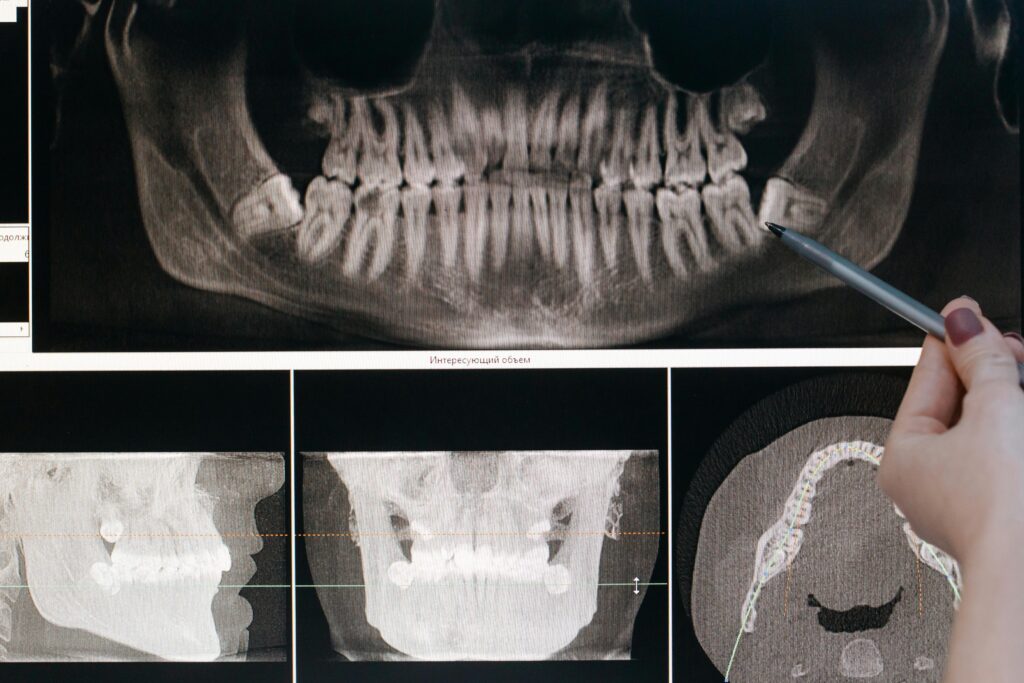

Step 3: X-Rays (If Needed)

Not always done every visit. X-rays help spot issues between teeth and under the gums.